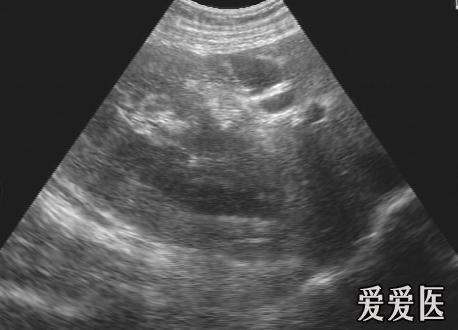

肾脏挫裂伤 - 超声医学讨论版 - 爱爱医医学论坛

图片尺寸768x576